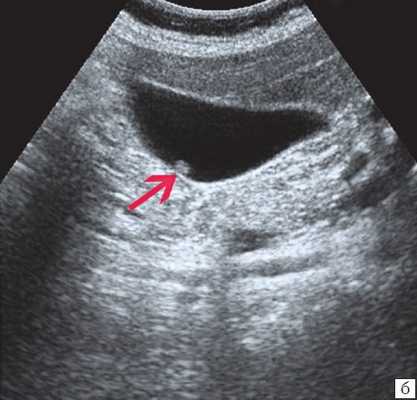

(Слева) На сонограмме у мужчины 79 лет с жалобами на боль в правом подреберье определяется утолщение стенки желчного пузыря, в передней стенке визуализируется эхогенный участок вытянутой формы. Обратите внимание на «грязную» заднюю акустическую тень - сонографический артефакт, характерный для газа.

(Справа) На поперечной сонограмме у этого же пациента определяются интрамуральные включения газа дающие «грязную» акустическую тень. Обратите внимание на инфильтрированный сальник, вплотную прилежащий к желчному пузырю, и слой небольших камней. При патоморфологическом исследовании подтвердился гангренозный холецистит.

6. УЗИ признаки эмфизематозного холецистита:

• Включения газа в стенке желчного пузыря выглядит высокоэхогенными, отражают ультразвук и дают плотную и «грязную» заднюю акустическую тень:

о Тень не анэхогенна (как это наблюдается в случае желчных конкрементов); характеризуется промежуточной эхогенностью

о Эхогенные отражающие включения ассоциированы с артефактами «дребезжания сигнала» или «хвоста кометы»

• Пузырьки газа в просвете желчного пузыря должны быть подвижными на УЗИ в режиме реального времени и могут «вскипать», напоминая пузырьки газа в шампанском (симптом «шампанского»):

о При изменении положения пациента включения газа могут смещаться

• Холелитиаз (у 50% пациентов), утолщение стенки желчного пузыря, свободная жидкость возле него, повышение эхогенности перипузырной жировой ткани, обусловленное воспалением